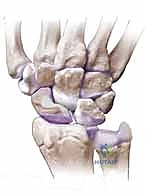

3. الروابط الرباطية الدقيقة والموقع الاستراتيجي

يحيط بالعظم الزورقي شبكة معقدة من الأربطة القوية التي تحافظ على استقرار الرسغ. يعمل الزورقي كـ "عمود خيمة" يربط الصفين العظميين في الرسغ. عندما ينكسر هذا العمود ولا يلتئم، تنهار الخيمة (الرسغ). ينثني الجزء البعيد من العظم الزورقي للأمام، ويميل الجزء القريب للخلف، مما يخلق تشوهاً يُعرف بـ "التشوه المحدب" (Humpback Deformity). هذا التشوه يغير ميكانيكا الرسغ بالكامل ويجب تصحيحه جراحياً.